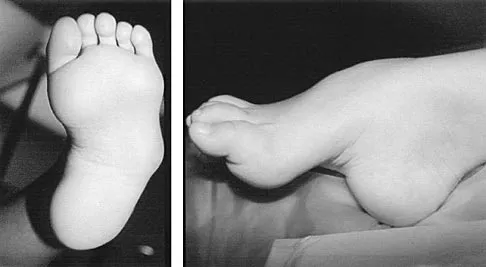

An 11-year-old girl sustained an injury to her right foot when a 500-lb headstone fell on it. The headstone was removed after 3 minutes. Radiographs show multiple midfoot fractures. Examination reveals severe pain that is worse with passive toe motion. Clinical photographs are shown in Figure 28. Management should consist of

Explanation